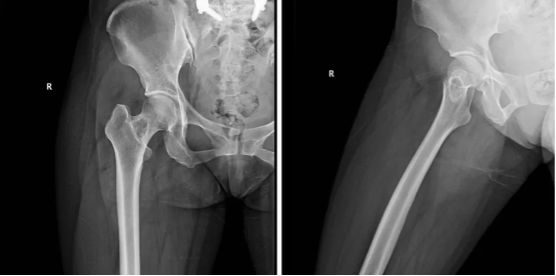

图1:术前X光片显示为右侧股骨颈部的边界清晰的骨质破坏